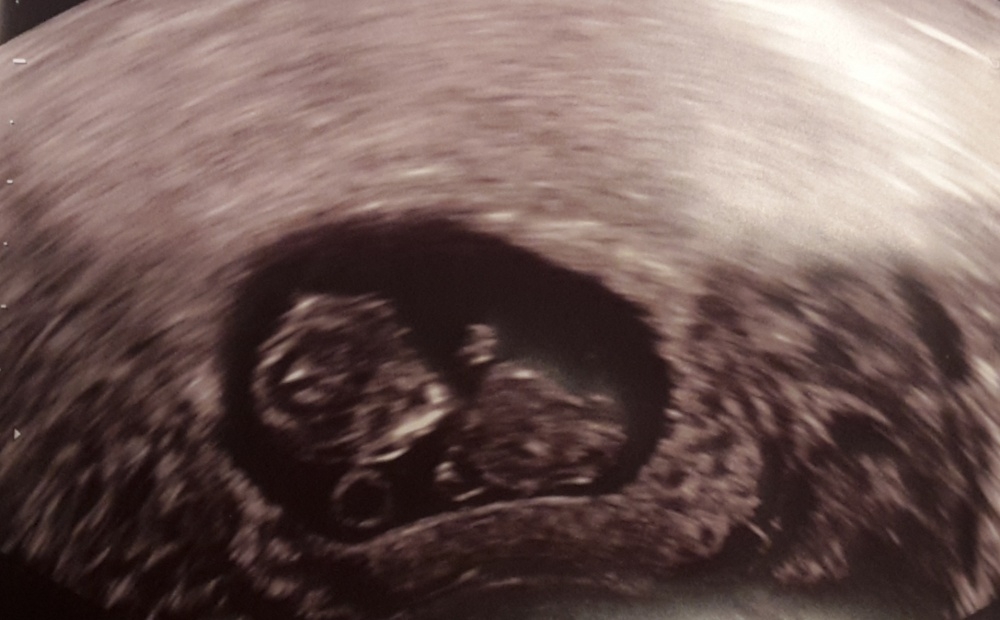

Ultraschall & Babyscans - Bub oder Mädchen? #1